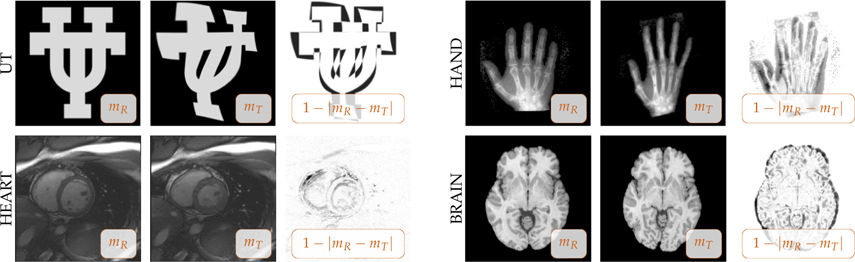

Medical Image Registration

\begin{equation} \min_\phi \int_\Omega \left(I_1(\phi(\ux))-I_0(\ux)\right)^2\dx + \Reg(\phi) \end{equation}

\( \class{hidden}{\phi(\ux)}\class{substep-3-phi}{\phi(\ux)}\class{substep-3-eq}{ = \ux+\ub(\ux)} \)\( \class{hidden}{\Reg}\class{substep-3-reg}{\Reg}^{\class{substep-3-eq}{\text{elas}}}\class{substep-3-eq}{(\ub) = \int_\Omega \frac{\mu}{4} \left(\nabla\ub + \nabla^T \ub\right)^2 + \frac{\lambda}{2}\left(\text{div}\, \ub\right)^2 \dx} \)

Nice physical interpretation:

Regularization forces displacement to follow a materials law